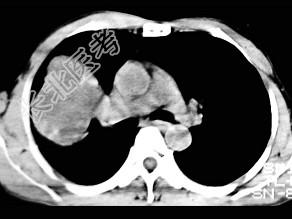

- 单项选择题根据所提供的图像,最可能的诊断是 ( )

A、肺内软骨肉瘤

B、胸膜间皮瘤

C、球形肺炎

D、机化性肺炎

E、局限性不张